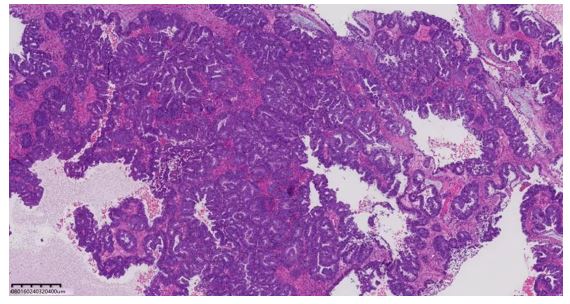

Following admission, the patient immediately underwent laparoscopic exploration. Intraoperatively, approximately 300 mL of dark-brown fluid was found in the pelvic cavity. The uterus was enlarged to the size of a 7-week gestation, smooth-surfaced, with multiple intramural fibroids (2.0–3.0 cm). The left fallopian tube was smooth; a left ovarian cyst was noted, 10×10 cm, with a smooth surface and a 1×1 cm rupture site leaking dark-brown fluid, but no active bleeding. The left cyst was densely adherent to the left fallopian tube, posterior and anterior uterine walls, and posterior leaf of the left broad ligament. Multiple right ovarian cysts (1–2 cm, smooth surface, intact capsule) were densely adherent to the posterior leaf of the right broad ligament; a millet-sized nodule and multiple yellow vesicular endometriotic lesions were found on the right fallopian tube. Both sacrouterine ligaments were contracted, with significant rigidity ("finger-like" on the left), and the left round ligament and adjacent soft tissue were firm, with marked retroperitoneal thickening. Part of the greater omentum was densely adherent to the anterior abdominal wall; yellow vesicular changes (3×3 mm) were noted along the left peritoneum near the round ligament. The bowel, mesentery, omentum, liver, spleen, and diaphragm appeared smooth with no obvious lesions; a flat black dot-like lesion (diameter ~4 mm) was observed on the peritoneum anterior to the liver, suspicious for endometriosis. During dissection, a cauliflower-like solid mass (4×3 cm) was found within the left cyst. As this was an emergency surgery, only the right adnexa was excised intraoperatively, with another elective surgery planned. Postoperative pathology: high-grade endometrioid carcinoma (endometrioid carcinoma, HEC) of the left side, with background evidence of endometriosis. Endometriosis was also observed on the serosa of the left fallopian tube. On postoperative day 1, repeat serum amylase was 75.4 U/L. Cytology from ascites was negative for tumor cells. Due to poor intestinal condition, a second staged surgery was planned.

Gynecological acute abdomen is an emergency primarily characterized by abdominal pain, often accompanied by other symptoms. Etiologies include malformations, infections, endometriosis (endometriosis, EMs), gynecologic tumors, surgical complications, or special circumstances, with peri- or postmenopausal cases largely attributed to tumors, trauma, or dysfunctions [1]. Acute abdomen progresses rapidly; failure to promptly and accurately diagnose and treat may result in shock and life-threatening conditions, representing surgical indications. Clinical symptoms, ultrasound, imaging, laparoscopy, and laboratory tests are the fundamental diagnostic approaches for evaluating causes of acute gynecologic abdomen [2]. This patient (46 years old) presented with abdominal pain mainly due to tumor etiology. Comprehensive assessment using ultrasound, CT, laparoscopy, laboratory testing, and postoperative pathology led to the diagnosis of right-sided high-grade endometrioid carcinoma on the background of endometriosis, with endometriosis also involving the left fallopian tube serosa. Ovarian endometrioid carcinoma (OEC) is an epithelial malignancy originating in the ovary with histopathological features similar to endometrioid carcinoma of the endometrium. OEC has a significant association with endometriosis [3,4], consistent with our case. Regarding laboratory tests, CA-125 and other tumor markers are routinely assessed, but serum amylase measurement also warrants clinical attention. An elevation of amylase in serum or body fluids has been associated with various neoplasms of non-pancreatic origin. Among cancer-related studies, amylase-producing tumors predominantly include cases of lung cancer, carcinoma, and multiple myeloma [5,6,7]. Serum amylase is considered a promising tumor marker. Amylase-producing tumors may present similarly to pancreatitis, as hyperamylasemia is common among such malignancies [8]. The predominant tumor amylase phenotype is often of the salivary type [9,10]. The pancreas and salivary glands are physiological sources of amylase. Normally, amylase is present in the digestive tract; its presence in the blood may indicate pancreatic or salivary gland cell injury—such as in pancreatitis, bile duct obstruction, sialadenitis, diabetic ketoacidosis, traumatic brain injury, or abdominal aortic aneurysm—causing release of amylase into the blood and resulting in elevated serum amylase [11]. Literature review reveals Jie et al. reported a case of carcinoma with intestinal involvement and elevated amylase; the diagnosis postoperatively was high-grade serous carcinoma, with amylase levels declining after surgery and chemotherapy [12]. Logie JJ et al. also reported a case of a woman in her 50s with abdominal distension and serum amylase exceeding 30 times the upper normal limit; postoperative pathology revealed high-grade serous carcinoma with metastatic spread. After chemotherapy and surgical treatment, serum amylase and CA-125 significantly decreased [13]. Gao et al. described a 46-year-old female with elevated amylase, ruling out other causes such as pancreatitis, finally diagnosed with advanced serous carcinoma [14]. In addition, Tohya T reported a 45-year-old patient with endometrioid adenocarcinoma associated with hyperamylasemia and liver metastases [15]. O'Riordan T reported a patient with serous surface carcinoma associated with abnormal amylase elevation [16]. Collectively, most reported cases are of serous carcinoma pathology; the current case, however, represents a rare instance of high-grade endometrioid carcinoma secondary to malignant transformation of an endometriotic cyst, accompanied by elevated amylase—an uncommon pathological type in previous reports. This suggests that carcinoma accompanied by elevated amylase may present in diverse pathological types. Several studies strongly suspect that tumor cells themselves produce amylase; however, further studies are needed to validate amylase as a significant tumor marker for endometrioid-type carcinomas. This case serves as supplementary evidence for clinical consideration, highlighting that in cases of acute abdominal pain with elevated serum amylase, malignancy should be considered in addition to acute pancreatitis. Carcinoma is a common gynecologic malignancy. CA-125 and CA-199 are standard tumor markers, but their specificity is limited. In clinical practice, large cystic tumors are frequently encountered, and imaging alone may not reliably differentiate between benign and malignant lesions. A novel marker would assist in determining tumor nature. For massive tumors—especially when presenting as acute abdomen requiring emergency surgery—serum amylase testing may offer further insight into the tumor's character and may inform the feasibility of large-scale screening for carcinoma.